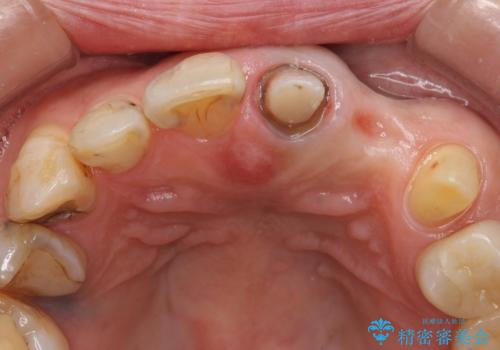

左上1、2番目の歯は仮歯の状態だったので外して状態を確認したところ、左上2は垂直的な歯根破折を認めたため抜歯となりました。左上1は再根管治療を行いました。

左上2抜歯後、骨および歯肉の回復を待ち、オールセラミッククラウンのブリッジによる欠損補綴を行いました。